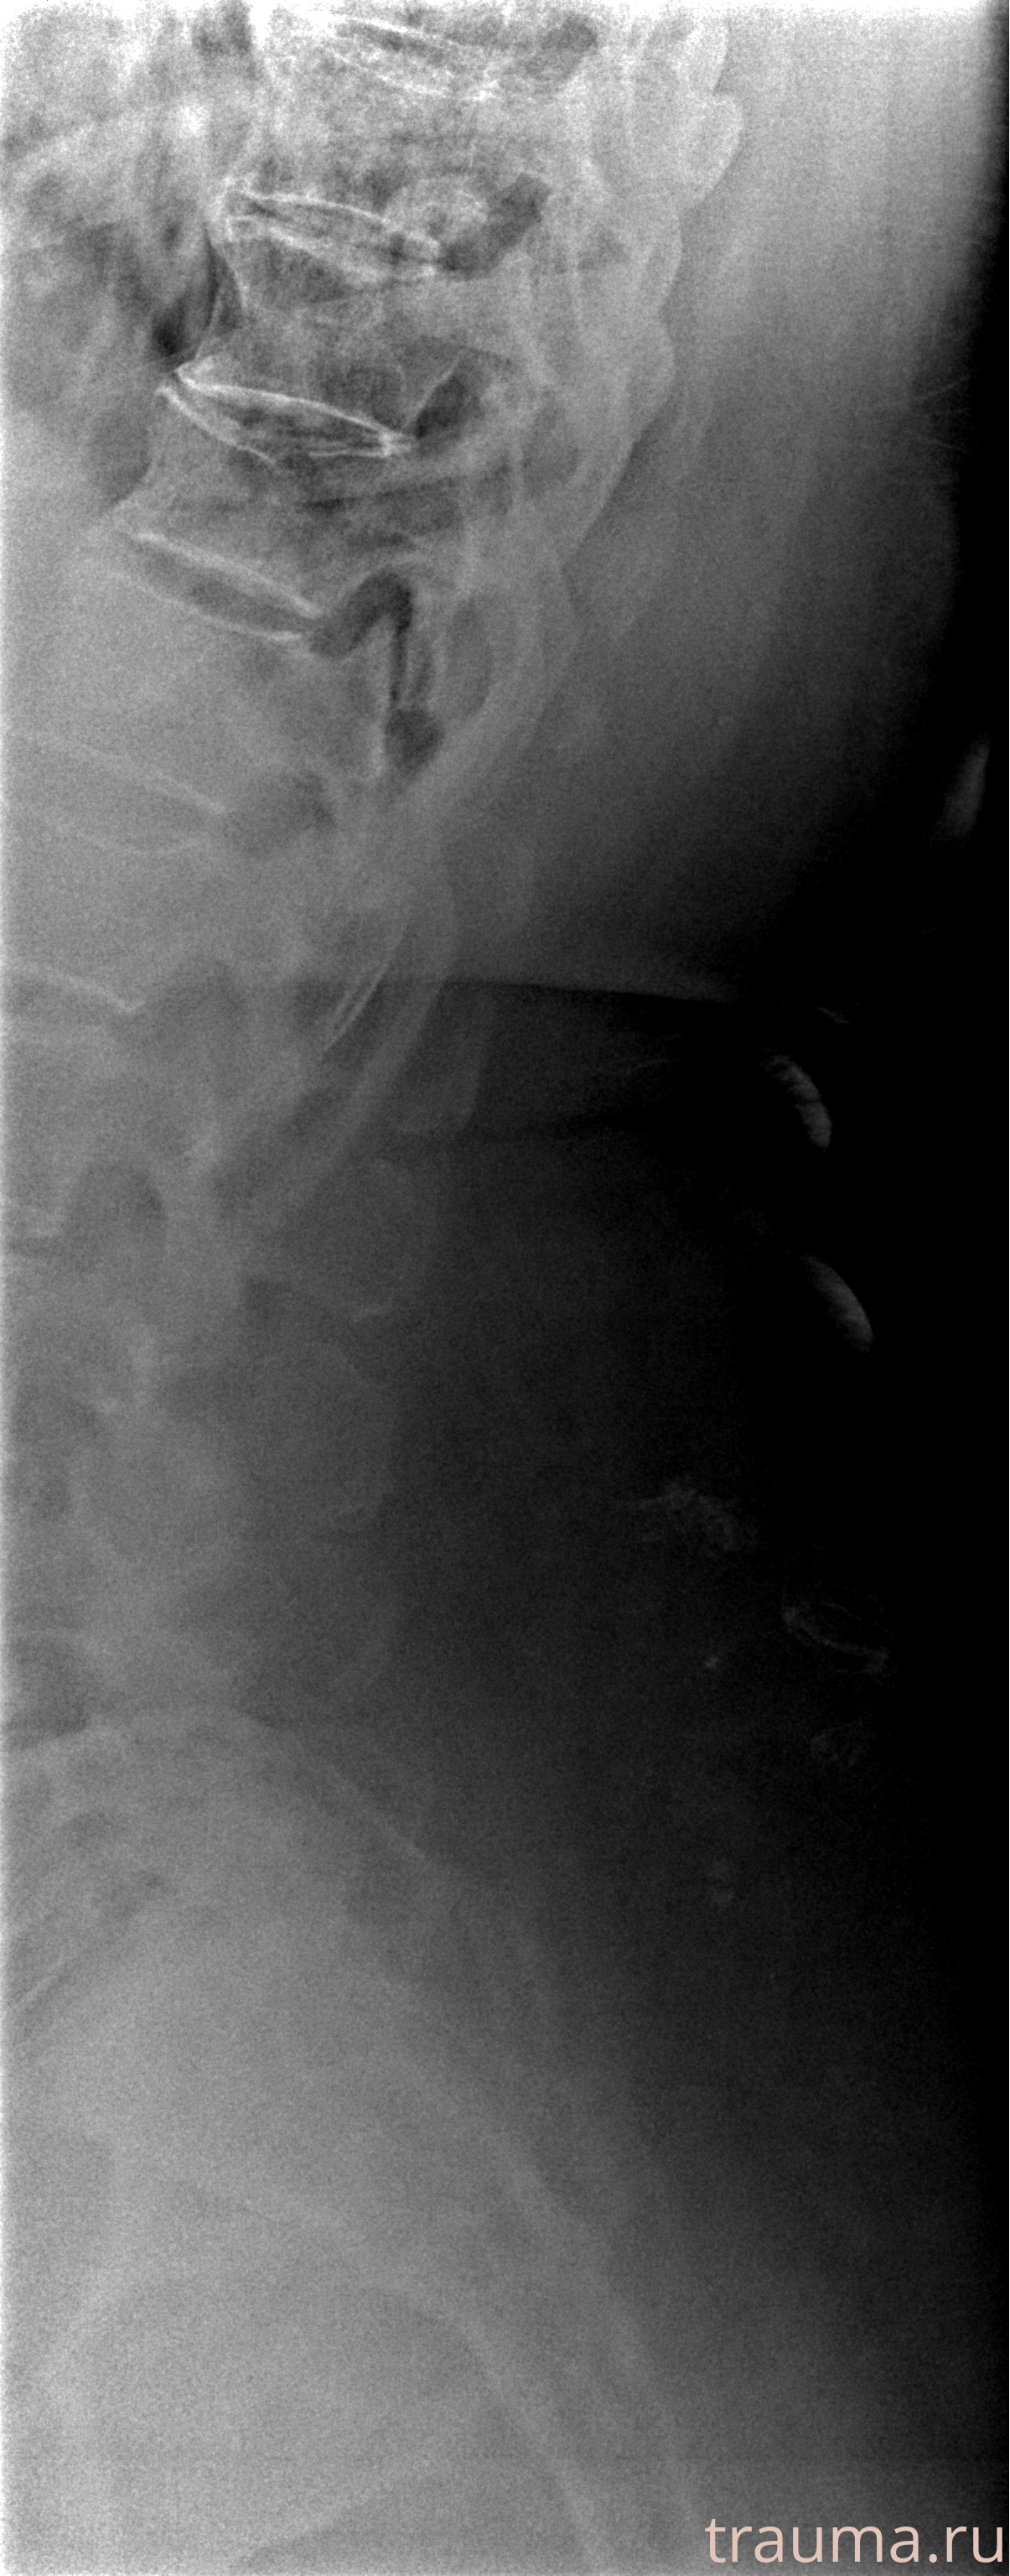

Рентген на дому: по вашему адресу приезжает врач-рентгенолог, травматолог-ортопед с мобильным рентгеновским аппаратом, проводит диагностику травмы или заболевания, делает необходимые рентгенограммы, дает рекомендации по дальнейшему лечению. Получить качественные снимки в домашних условиях возможно благодаря уникальной методике, разработанной МосРентген Центром для института  Склифосовского